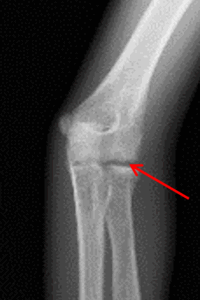

・X線検査:骨、成長軟骨の異常、剥離骨片の有無などを検査

内側型

・内側上顆骨軟骨障害(リトルリーグ肘) 以下のように呼ばれることもあります。

内側上顆骨端障害

内側上顆下端裂離骨折

・内側上顆骨端線損傷 以下のように呼ばれることもあります。

骨端線閉鎖不全

内側上顆骨端離開

・内側側副靭帯損傷